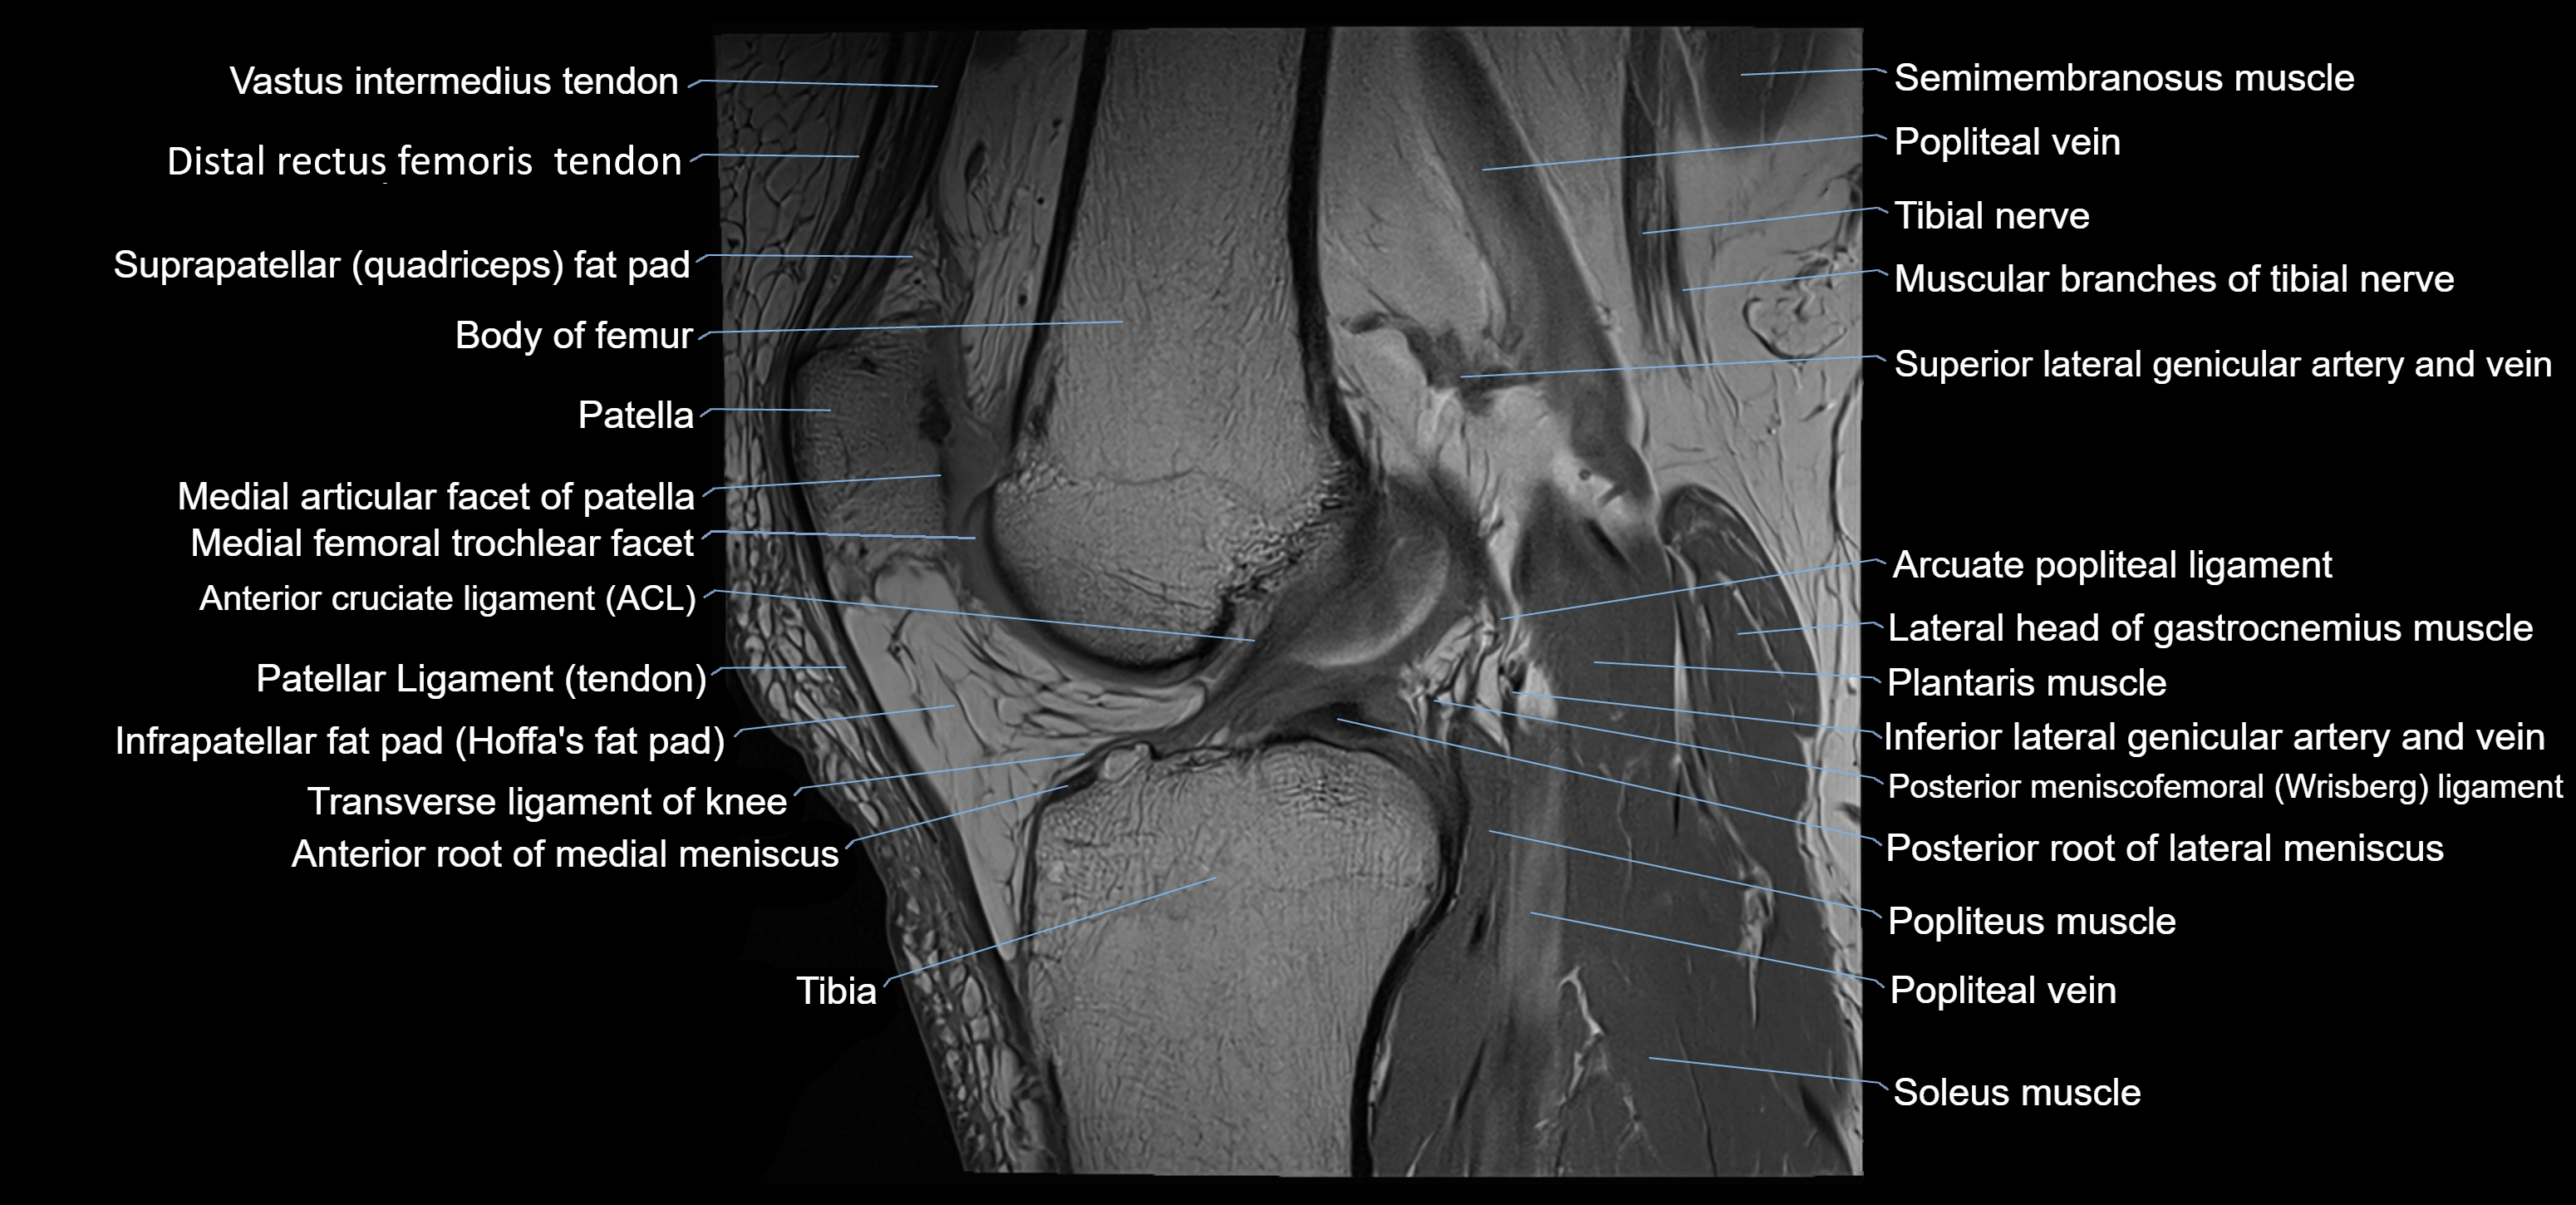

- Anterior cruciate ligament

- Anterior horn of lateral meniscus

- Anterior horn of medial meniscus

- Anterior meniscofemoral ligament

- Anterior root of lateral meniscus

- Anterior root of medial meniscus

- Arcuate popliteal ligament

- Infrapatellar fat pad

- Intercondylar eminence

- Medial articular facet of patella

- Medial meniscus

- Patella

- Patellar articular cartilage

- Patellar tendon (patellar ligament)

- Popliteal vein

- Popliteus muscle

- Posterior cruciate ligament

- Posterior meniscofemoral ligament

- Posterior root of lateral meniscus

- Posterior root of medial meniscus

- Semimembranosus muscle

- Soleus muscle

- Tibia

- Tibial nerve

- Transverse ligament of knee